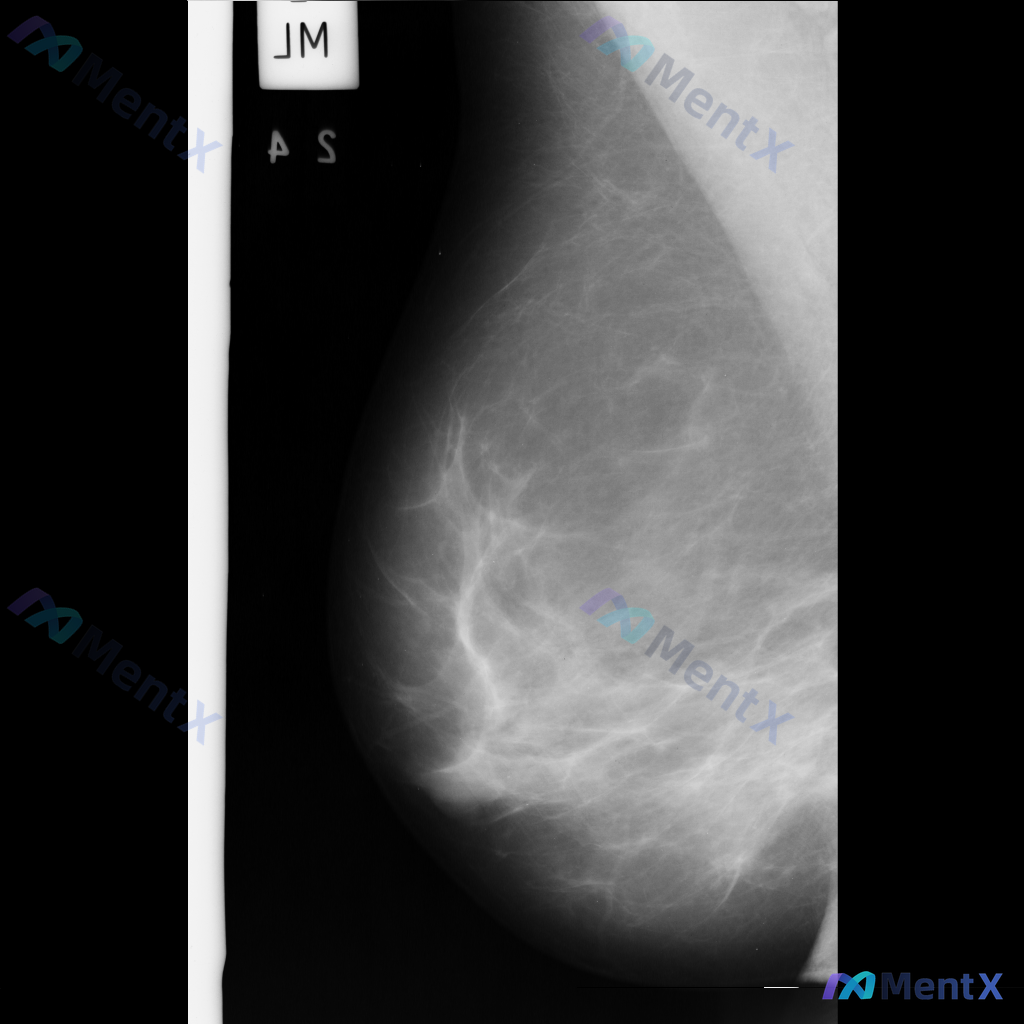

整理到一份乳腺钼靶影像的病例资料,目前只有单侧MLO位片: 影像表现:在乳腺中央偏上方区域可见一个高密度、类圆形的单个钙化影,边界清晰,大小约2-3毫米。目前没有看到明确的肿块、结构扭曲或不对称致密影等其他可疑征象。 想请教大家,单看这组单侧MLO位的影像表现,你会先怎么判断这个钙化的性质倾向?后续...